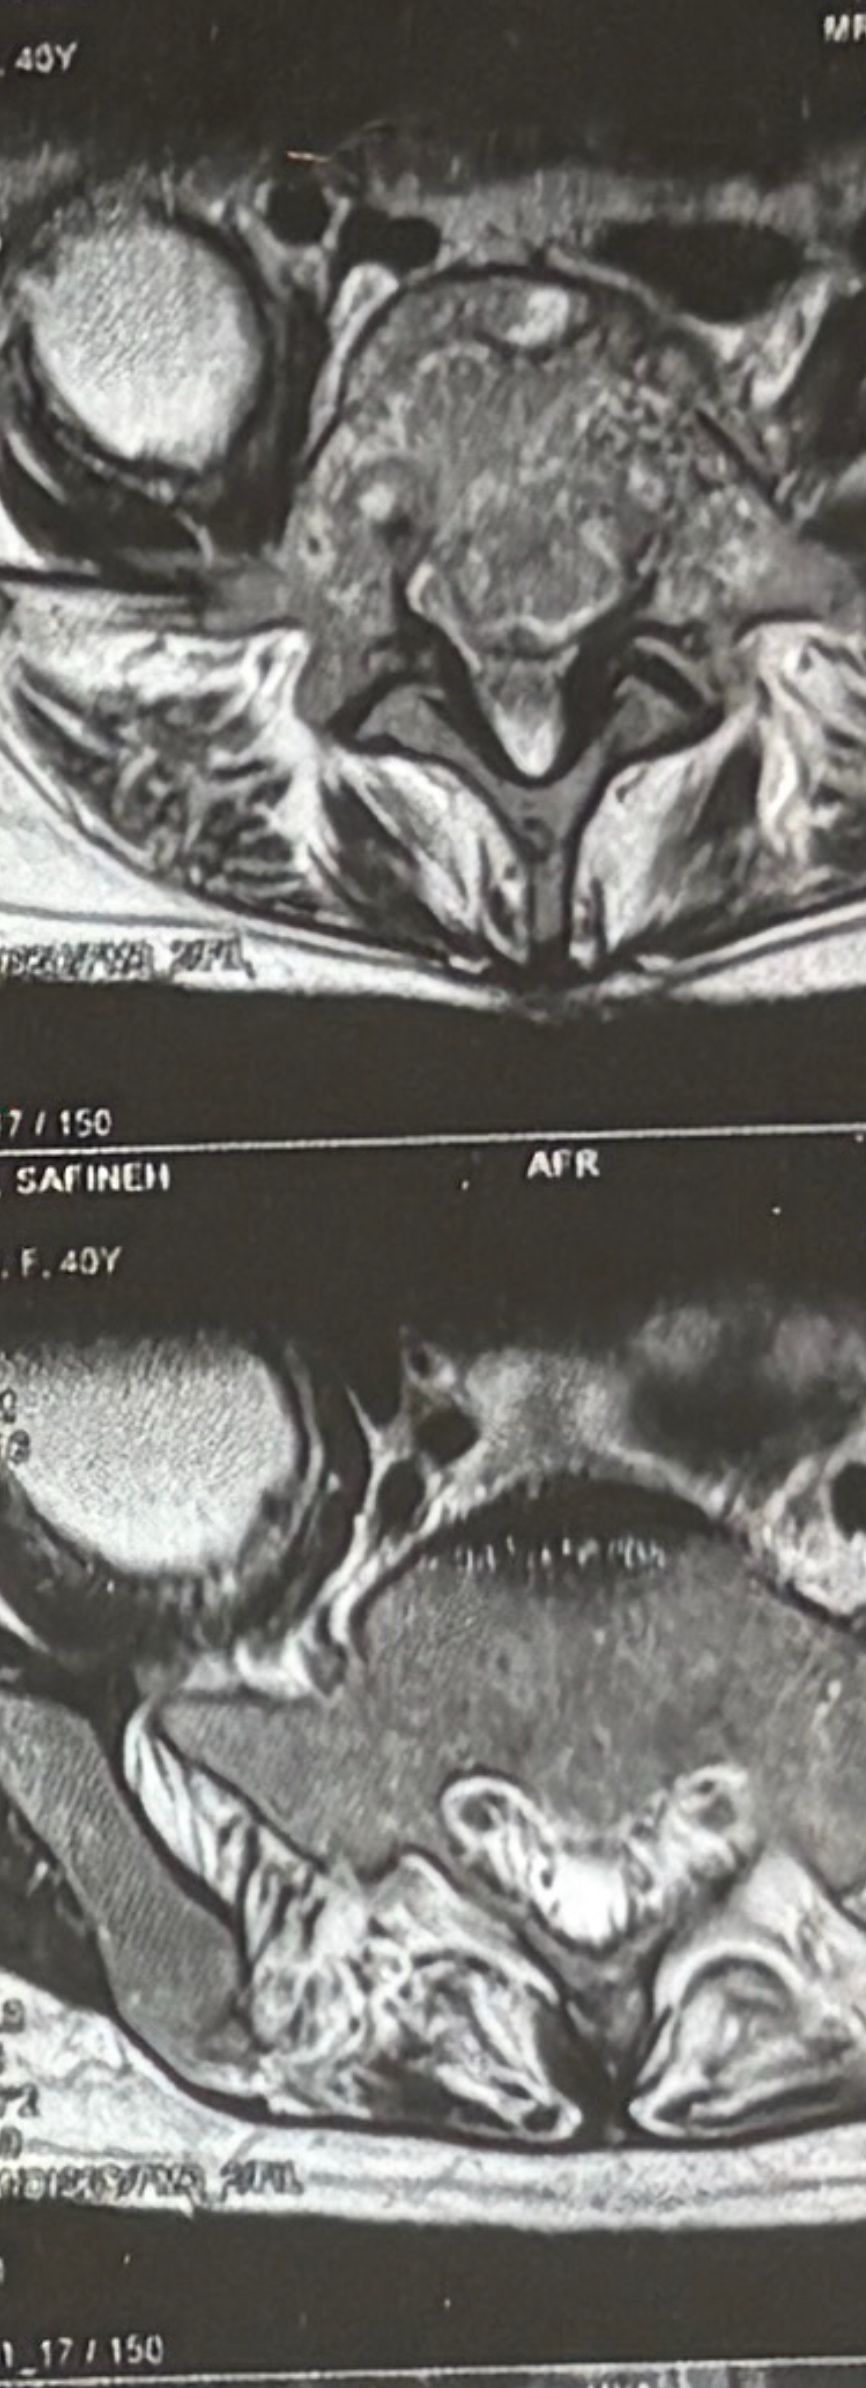

Case 11

40 yrs old female patient presented to my office on Feb 08/2025 with severe R post shoulder pain along C6-5 dermatome since 3 weeks ago.Had physiotherapy, didn’t help. Her mri 3 months ago and the new one few days ago were the same and showed R. para R. IVF C5-6 moderate size protrusion. Her exam was normal. After 5-6 sessions of treatment she has got 60 percent improvement P